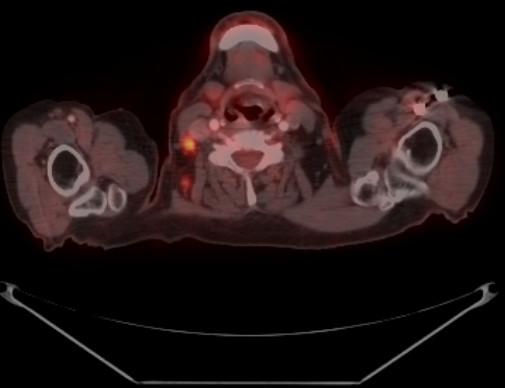

Records of patients who underwent PET probe-guided surgery were reviewed. Surgical indications and operative targets were determined based on diagnostic PET/PET-CT images performed prior to probe-guided surgical planning. PET probe-guided surgery was performed on a separate day using a high-energy gamma probe (PET probe, Care Wise Medical, Morgan Hills CA) 2-6 hours post-injection of 5-15 mCi FDG. Probe count rates, target-to-background ratios, and lesion detection success were analyzed.

Twenty-four patients underwent PET probe-guided surgery; one patient had two PET-probe guided surgeries resulting in a total of 25 cases (5 colorectal cancer cases, 4 thyroid cancer cases, 6 lymphoma cancer cases, and 10 other cancer cases). Surgical indication was diagnostic exploration in 6 cases with lymphoma and 1 case with head and neck cancer (28%). The remaining 18 cases (72%) underwent PET probe-guided surgery with a therapeutic intent in a recurrent or metastatic disease setting. All the lesions identified and targeted on a preoperative FDG-PET scan were detected by the PET probe with satisfactory in-vivo lesion count rates and a TBR of >/= 1.5. PET probe allowed localization of lesions that were non-palpable and non-obvious at surgical exploration in 8 patients.

回顾接受PET探头引导手术患者的记录。根据探头引导手术规划前进行的诊断性PET/PET-CT图像确定手术适应症和手术靶点。在注射5-15 mCi氟代脱氧葡萄糖(FDG)后2-6小时,使用高能伽马探头(PET探头,Care Wise Medical,加利福尼亚州摩根山)在单独的一天进行PET探头引导手术。分析探头计数率、靶本底比和病灶检测成功率。

24例患者接受了PET探头引导手术;1例患者接受了两次PET探头引导手术,共25例(5例结直肠癌、4例甲状腺癌、6例淋巴瘤和10例其他癌症)。手术适应症为6例淋巴瘤和1例头颈癌的诊断性探查(28%)。其余18例(72%)在复发或转移性疾病背景下接受PET探头引导手术,具有治疗目的。术前FDG-PET扫描中识别和靶向的所有病灶均被PET探头检测到,体内病灶计数率令人满意,靶本底比≥1.5。PET探头使8例患者在手术探查中定位了触诊不到且不明显的病灶。